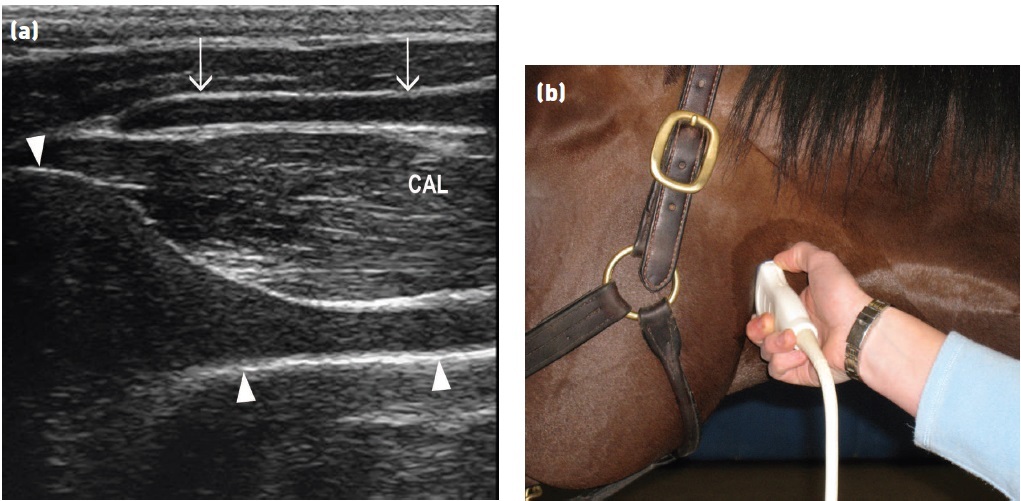

Fig 3: (a) Transverse plane ultrasound of the lateral aspect of a normal larynx. Note the position of the cricoarytenoideus lateralis

muscle (CAL) between the thyroid cartilage (arrows) and the arytenoid cartilage

(arrowheads)

.

The vocalis muscle is deep to the CAL, but the distinction between the muscles can often not be seen, as in this case. The arytenoid cartilage has a trumpet bell shape and the cricoarytenoideus lateralis and vocalis muscles have a striated appearance with heterogeneous echogenicity.

Dorsal is to the left of the image and ventral is to the right (b) Position of the transducer